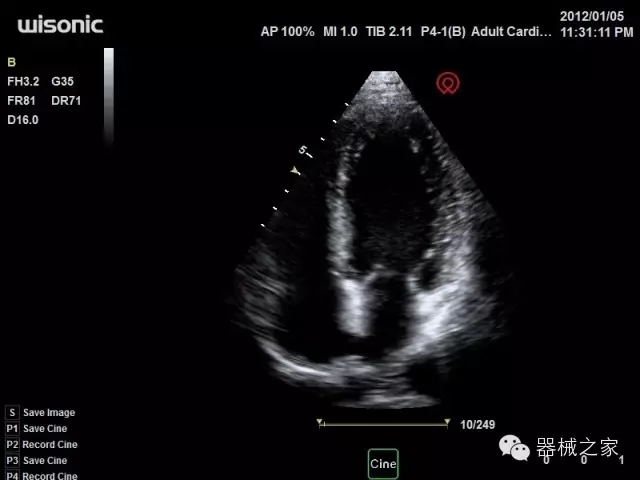

臨床圖片賞析

產(chǎn)品特點(diǎn)

·全球目前唯一一款配備主機(jī)雙探頭接口,整機(jī)重量(含電池)在5公斤以內(nèi)的便攜式彩超;

·一款互聯(lián)網(wǎng)彩超,只要有手機(jī)信號的地方就可以非常方便地實(shí)現(xiàn)遠(yuǎn)程會診和病案調(diào)?。?/span>

·鎂鋁合金外殼,堅(jiān)固可靠耐用;

·獨(dú)有的HoloTM PW 實(shí)時3取樣門PW成像技術(shù),精確進(jìn)行血管診斷;

·一鍵優(yōu)化B、Color、PW,Auto Doppler自動識別血管位置、偏轉(zhuǎn)角度等,提高工作效率;

·30°超廣角精細(xì)偏轉(zhuǎn)成像技術(shù),更優(yōu)異的頻譜圖像;

·W+智能搜索引擎,快速尋找圖像;

·SSD、USB3.0保障開機(jī)快,導(dǎo)出圖像更快,減少等待時間;

·WIFI、網(wǎng)口、3G,多重聯(lián)網(wǎng)方式,全天候保障云端備份,不再擔(dān)心圖像丟失;